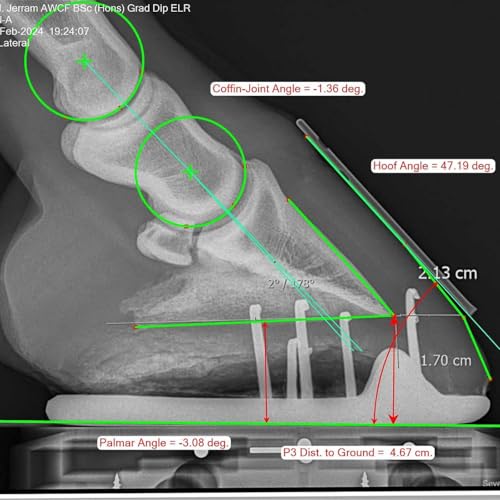

En este episodio de El Compañero del Cuidado del Casco, exploramos el papel crítico de la radiografía en la evaluación del equilibrio del casco equino. Tradicionalmente, herradores y veterinarios confiaban en la evaluación visual y táctil para guiar el recorte y el calzado, pero la imagenología diagnóstica moderna ha transformado el cuidado del casco.Únete al anfitrión Marc Jerram mientras exploramos cómo las radiografías brindan una visión más profunda de la alineación del casco, el eje del menudillo, los ángulos palmares, la profundidad de la suela y el equilibrio mediolateral. Discutimos cómo estas mediciones influyen en las decisiones del herrador, la colaboración entre veterinarios y herradores, y cómo la evaluación radiográfica puede mejorar tanto el cuidado preventivo como terapéutico del casco.Seas herrador, veterinario o profesional equino, este episodio ofrece conocimientos prácticos y perspectivas basadas en casos que pueden aumentar tu comprensión del equilibrio del casco y mejorar el bienestar y el rendimiento de los caballos bajo tu cuidado.